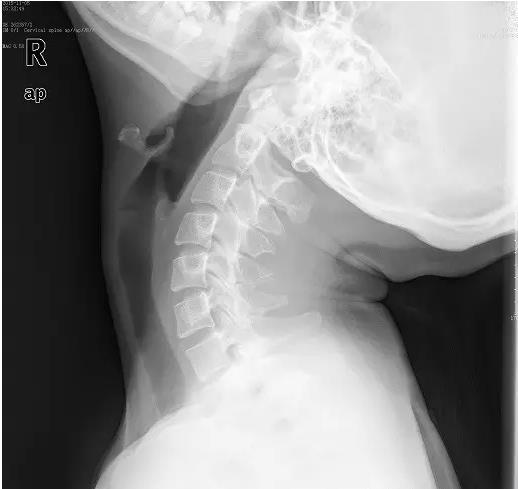

近日门诊接诊了一位18岁的花季少女小美,说是颈部疼痛难忍,已经半个月了,实在疼的不行了才来医院看看。拍片后显示:颈椎退变,生理弧度消失、变直。下面这张就是小张的颈椎侧位片。片子上,颈椎排列略呈“S”形。而不象是正常的“C”形。

有点医学常识的人都知道,正常脊柱由颈椎、胸椎、腰椎、骶尾椎组成。每一段都有相应的弯曲。其中颈椎前凸、胸椎是后凸,腰椎是前凸,骶尾椎又是后凸。

这样,整个脊柱就有一定的弹性,人在运动时脊柱上受力就有一定的缓冲,同时便于发力,就像撑杆跳高的杆子一样。如果颈椎的生理弧度减少、变直、甚至反屈畸形,就不能发挥上述作用,长此以往,就会加速颈椎间盘的退变,加速颈椎骨质增生,最终造成严重的颈椎病。